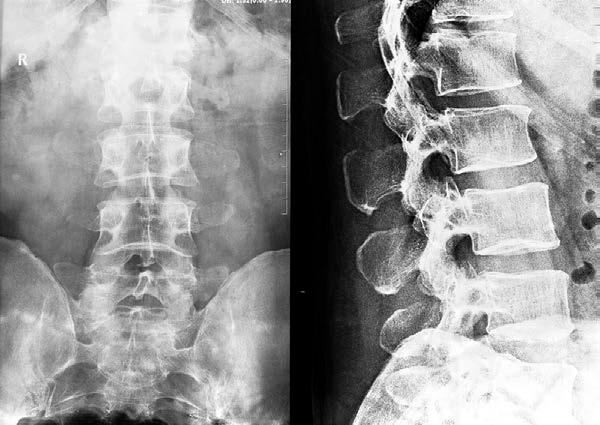

AudioLearn's Medical School Crash Courses presents Radiology

Written by experienced professors and professionally narrated for easy listening, this crash course is a valuable tool both during school and when preparing for the USMLE, or if you’re simply interested in the subject of Radiology.

The audio is focused and high-yield, covering the most important topics you might expect to learn in a typical Medical school Radiology course. Included are both capsule and detailed explanations of critical issues and topics you must know to master Radiology. The material is accurate, up to date and broken down into bite-sized sections. There are key takeaways following each chapter to drive home key points and quizzes to review commonly tested questions.